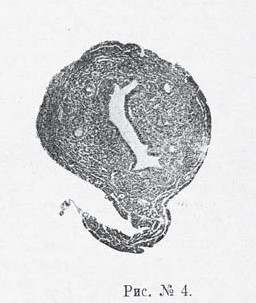

недостаточность (см. рис. № 3). В матке количественная разница выступала еще резче (см. рис. № 4). Соответственно уменьшению всего органа оказывались недоразвитыми и все его составные части,—мышечный слой и слизистая оболочка были слабо развиты, железы уменьшены и в количестве и величине, интерстициальная ткань слизистой слабо выражена (производит впечатление атрофии), покровный эпителий ниже нормального, просвет матки уменьшен. Следовательно, и здесь имела место картина общей задержки развития матки, остановки на известной стадии детского состояния ее, инфантилизма,/даже более того—ее гипоплязии.

Рис. № 3. Рис. № 4.